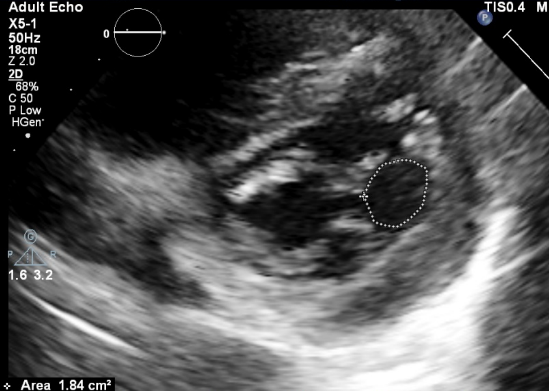

男性,72岁,因“喘憋3年,加重一天”于我院急诊科就诊。急诊床旁经胸超声示:左房扩大,LVEF:66%;短轴似呈双孔开放(考虑为先天性双孔型畸形):后内侧孔较大,开放面积约2.8c㎡,前外侧孔较小,开放面积约1.8c㎡(图1、2、3)。前外侧孔P1区脱垂,伴重度反流,VCW:10.2mm。后内侧孔亦可见少量中心性反流。三尖瓣反流法估测肺动脉收缩压55mmHg。

△图1